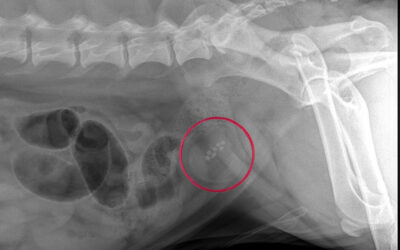

Fallbericht FLUTD

Der 5-jährige kastrierte Kater „Chiko“ wurde wegen ausbleibendem Harnabsatz vorgestellt. Zuvor zeigte er starke Schmerzen beim Urinieren. Drei Wochen früher war er wegen blutiger Zystitis behandelt worden, hatte sich zunächst erholt, entwickelte dann aber erneut...

FLUTD bei Katzen – Behandlung, Therapie und Vorbeugung

FLUTD (Feline Lower Urinary Tract Disease) ist ein Sammelbegriff für verschiedene Erkrankungen der unteren Harnwege bei Katzen – vor allem Katern. Die Behandlung hängt stark davon ab, wie schwer die Erkrankung ist und was sie ausgelöst hat. Wenn die Harnröhre...

FLUTD bei Katzen – Was ist das und worauf sollte man achten?

FLUTD (Feline Lower Urinary Tract Disease) ist ein Sammelbegriff für Erkrankungen der unteren Harnwege (Blase und Harnröhre) bei Katzen – besonders häufig betroffen sind männliche Tiere (Kater). Warum trifft es vor allem Kater? Die Harnröhre im Penis eines Katers ist...

Harnsteine bei Kleintieren

Harnsteine (Urolithiasis) treten bei Hund, Katze und Heimtieren relativ häufig auf. Kleine Kristalle können unbemerkt mit dem Urin ausgeschieden werden. Werden die Steine jedoch größer, blockieren sie enge Stellen der Harnwege (Harnleiter, Blasenausgang, Harnröhre)...